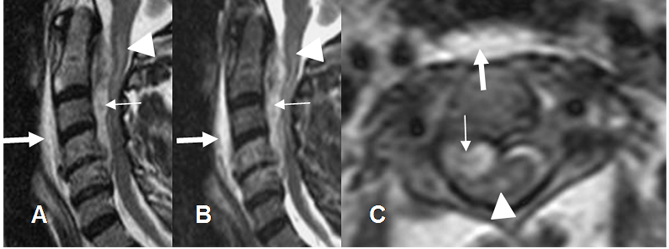

Fig 142 A. Empiema epidural.

A: RM sagital en T2, B: RM sagital en STIR y C: RM axial en T2. Espondilodisquitis C4-C5, con disminución del espacio intervertebral. Se encuentra colección epidural entre C2 y C5 que comprime el saco dural (Flechas delgadas) y prevertebral (Flechas gruesas). Adicionalmente hay hiperintensidad medular, por mielopatía secundaria. (Puntas de flecha).

Fig 142 B. Empiema epidural.

A: RM sagital en T1 simple, B: RM sagital en T1 y C: RM axial en T1 con contraste. Igual paciente anterior. Espondilodisquitis C4-C5, con colección epidural cuyos bordes realzan con el contraste y comprime el saco dural.